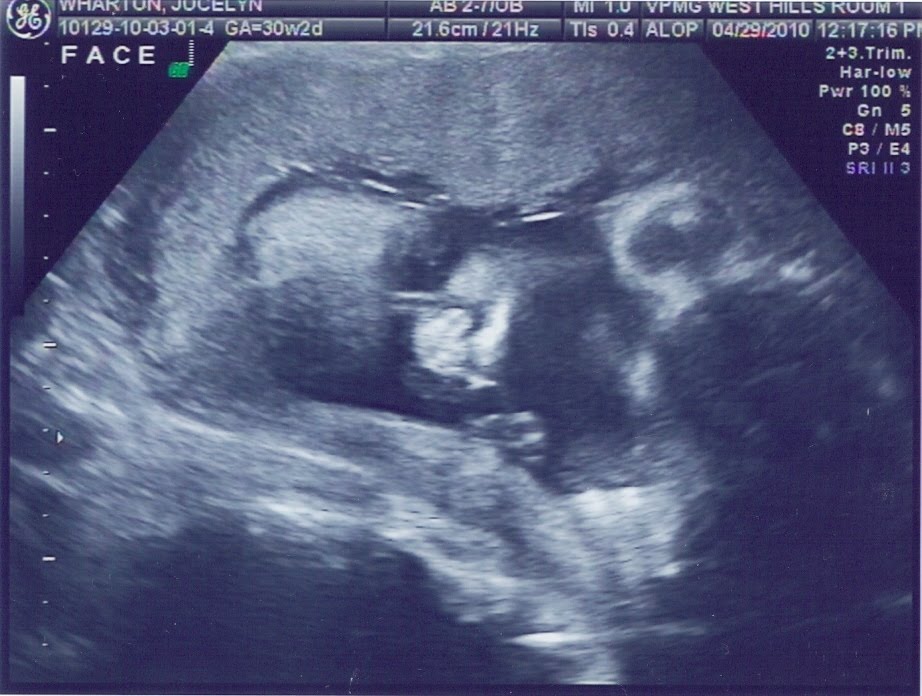

Sugar and Spice and Everything Nice. That’s what little girls are made of!

IT’S A GIRL!!